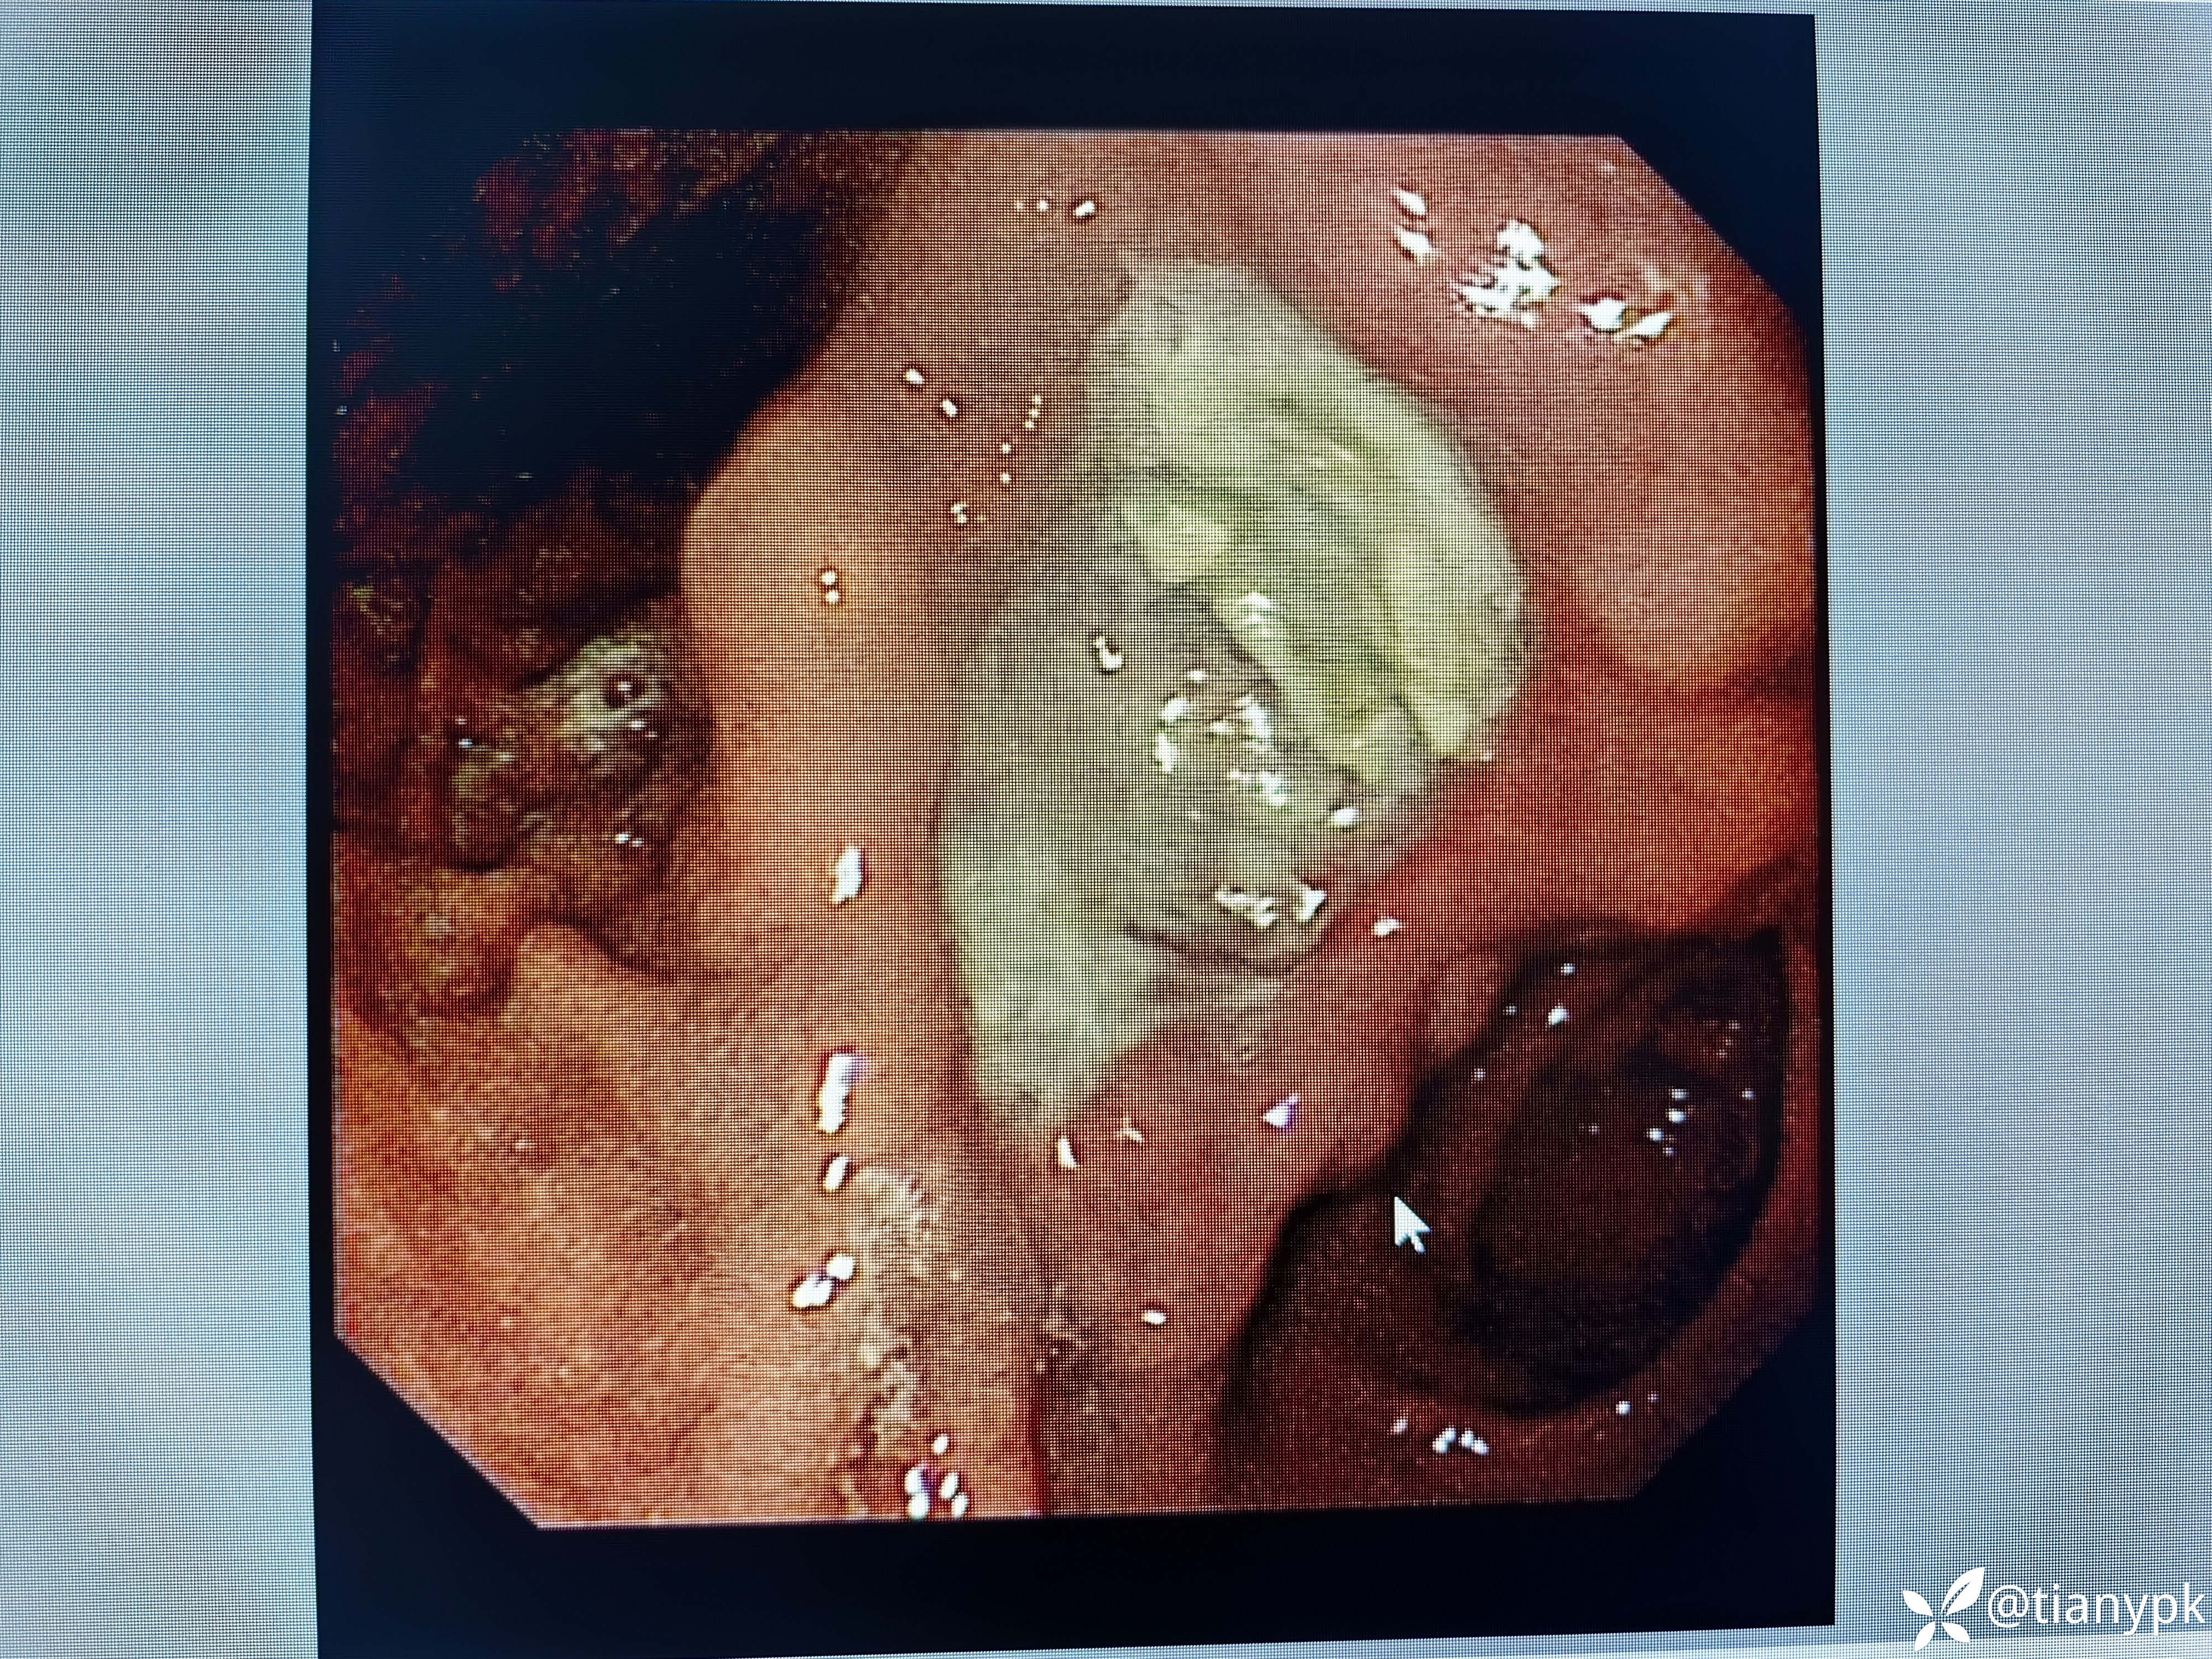

男性,54岁。

主诉:中上腹隐痛一周余伴大便发黑。

既往有乙肝,长期抗病毒治疗,否认近期明显消瘦。

胃镜检查如下:

胃角见巨大溃疡,良性?恶性?

活检大家一般取几块?